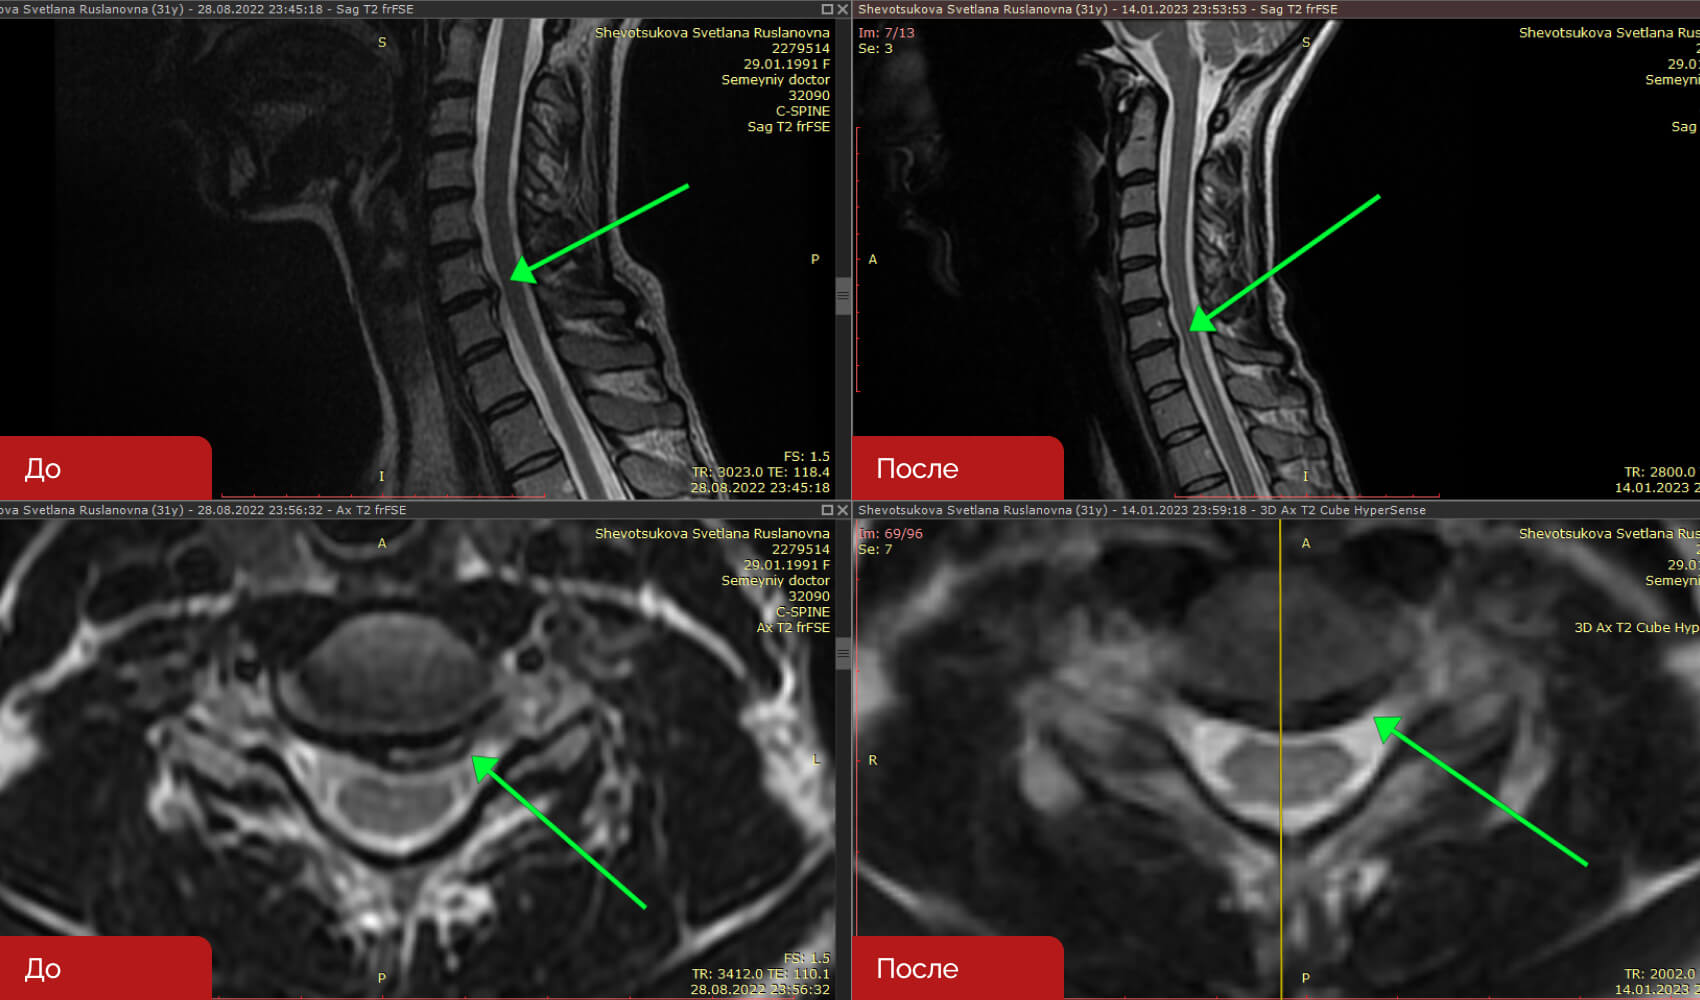

Резорбция грыж — это терапевтический процесс, направленный на уменьшение или полное исчезновение межпозвонковых грыж без хирургического вмешательства. Данный метод включает серию около 12 посещений клиники, три раза в неделю. После курса процедур, врач определяет время контрольного МРТ (обычно 2-3 месяца) для оценки результатов лечения.

Не все грыжи поддаются лечению данным методом. Решение о назначении резорбции принимается на основе анализа жалоб пациента, результатов МРТ и срока давности грыжи. Метод является безопасным и отличается отсутствием осложнений.

Кейс 2